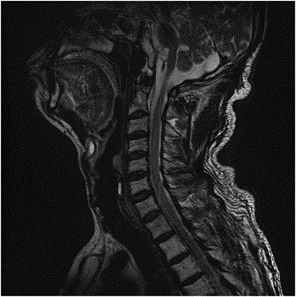

Các phương tiện chẩn đoán bao gồm siêu âm, MRI, PET/CT và xạ hình xương. MRI được xem là tiêu chuẩn vàng trong đánh giá đám rối cánh tay nhờ khả năng cung cấp hình ảnh giải phẫu chi tiết.

Trường hợp này mô tả bệnh nhân ung thư phổi di căn biểu hiện ban đầu bằng bệnh lý đám rối cánh tay, bị chẩn đoán nhầm là thoát vị đĩa đệm cổ cho đến khi phát hiện khối u trên đòn phải. Đặc điểm đau dữ dội, kéo dài không hoàn toàn phù hợp với hình ảnh thoát vị đĩa đệm.

Trong những trường hợp triệu chứng không được giải thích đầy đủ bằng MRI cột sống cổ, cần cân nhắc thực hiện MRI vùng lồng ngực hoặc đám rối cánh tay. Đáng chú ý, việc không quan sát rõ đám rối cánh tay trên siêu âm đã gợi ý chẩn đoán phân biệt quan trọng và dẫn đến phát hiện tổn thương di căn.